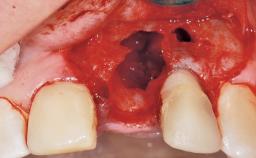

Late Placement of an Implant in a Maxillary Left Central Incisor Site

A 30-year-old female patient had lost tooth 21 and was referred to our clinic for consultation and treatment. Due to advanced apical infection, tooth 21 had been extracted two months earlier at another clinic and an acrylic-resin tooth had been bonded to the adjacent teeth. The patient desired implant treatment to avoid any damage to the adjacent natural teeth. While the patient had no history of any systemic disorder, she was a heavy smoker and exhibited medium to advanced periodontitis in the entire jaw. After the initial treatment to achieve a pocket probing depth of less than 4 mm and no bleeding on probing, a decrease in the height of the papillae mesial and distal to the extraction site and overall gingival recession were observed.